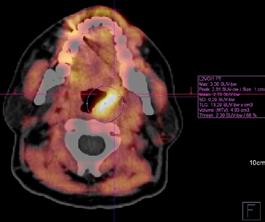

Badanie PET/CT łączy w sobie diagnostykę morfologiczną i metaboliczną poprzez jednoczesne wykonanie niskodawkowej tomografii całego ciała, obrazującej zmiany lityczne i ocenę zmian metabolizmu radioznacznika (najczęściej glukozy - 118F-fluorodeoksyglukoza, 18F-FDG) świadczących o aktywności choroby. Technika ta jest najskuteczniejszym narzędziem w identyfikowaniu zmian pozaszpikowych. Ponadto ma znaczenie rokownicze i jest przydatna

w monitorowaniu metabolicznej odpowiedzi na leczenie. Liczba i metabolizm zmian ogniskowych wykrytych w PET/CT wykonanym na wstępie leczenia indukcyjnego stanowi czynnik predykcyjny wyniku terapii (czasu wolnego od progresji i czasu przeżycia całkowitego) u pacjentów kwalifikujących się do transplantacji szpiku, a utrzymanie lub osiągnięcie statusu remisji w PET/TK po przeszczepie ma przełożenie na dłuższe czasy przeżycia.

Ryc. 4.3. 18F-FET PET/CT – solitary plasmacytoma migdałka podniebiennego lewego, miejscowo zwiększony wychwyt radioznacznika.

Ryc. 4.4. 18F-FET PET/CT – stan po zakończeniu leczenia.

W niektórych sytuacjach klinicznych interpretacja PET/ CT nie jest oczywista, potencjalnie obarczona błędem. Użycie 18F-FDG może być problematyczne w przypadku obrazowania zmian pozaszpikowych zlokalizowanych w regionach często objętych stanem zapalnym, między innymi w obrębie szyi (migdałki podniebienne), gdzie istnieje ryzyko uzyskania wyników fałszywie dodatnich. Wówczas korzystną alternatywę stanowią niestandardowe radioznaczniki (np. 18F-fluoro-etyl-L-tyrozyna, 18F-FET), które – w przeciwieństwie do FDG – nie ulegają kumulacji w miejscach zmienionych zapalnie, a przez to są bardziej specyficzne dla komórek nowotworowych. Należy pamiętać, że istnieje również ryzyko uzyskania wyników fałszywie ujemnych w przypadku przejściowej głębokiej supresji metabolizmu guza i konkurencyjnego hamowania wychwytu FDG z plazmocytów w sytuacji wzrostu glikemii, np. w trakcie steroidoterapii. Zmiany charakteryzujące się bardzo niskim stopniem wychwytu FDG, maskowane rozlanym wychwytem FDG lub w lokalizacji o silnej fizjologicznej aktywności FDG (np. w czaszce), mogą nie generować sygnału w badaniu PET.